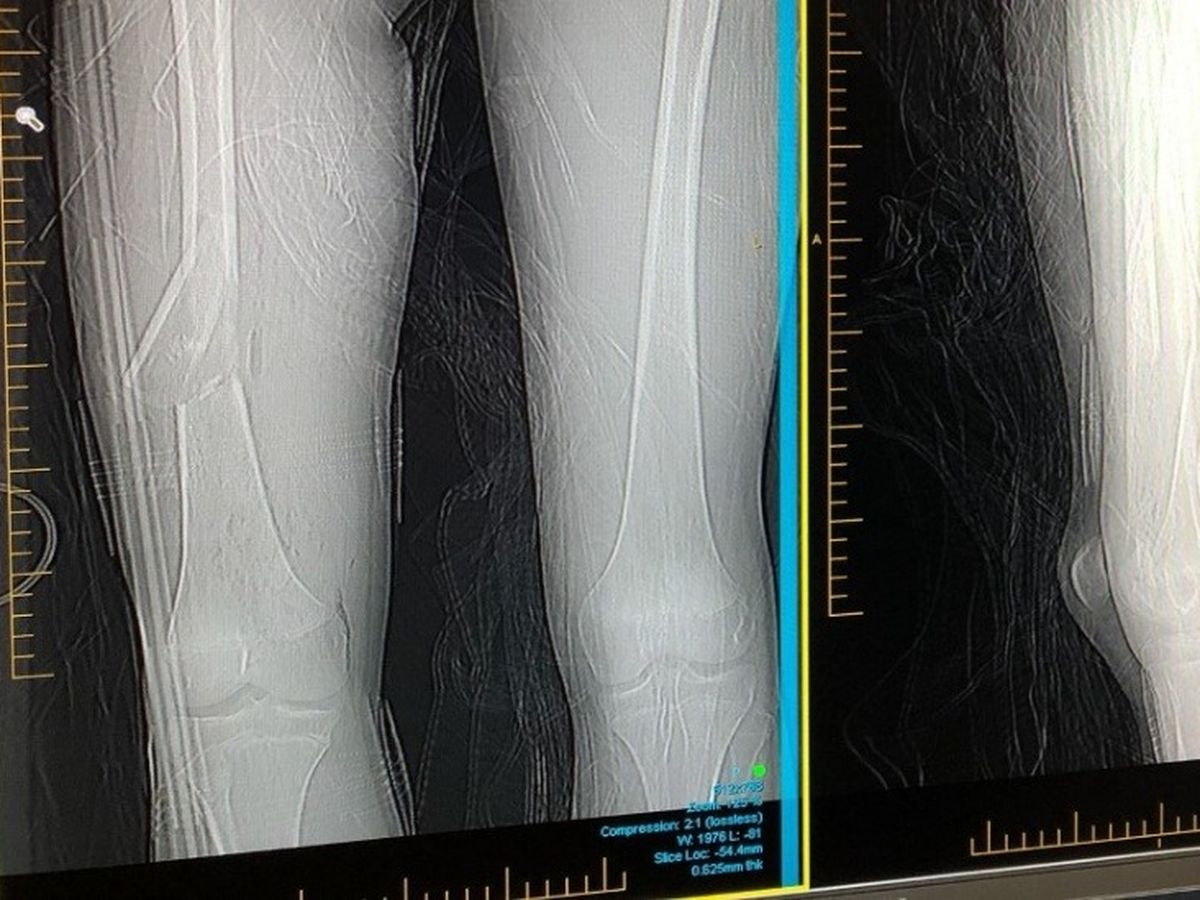

On Mon 2nd Dec our School based apprentice, Ryan Diver was hit by a car while riding his motorbike to work. He broke his femur and has multiple breaks in his right wrist. He was flown down to Perth by the wonderful RFDS where he received surgery at RPH. He now has a rod through his femur and may be going back down after Christmas for more surgery on his wrist. Ryan was planning on spending his school holidays working 6 days a week to save up some money. As he is no longer able to work during his holidays and to help cover some costs from the accident, we have decided to start a Go Fund Me for him. Any donations no matter how small would be greatly appreciated.